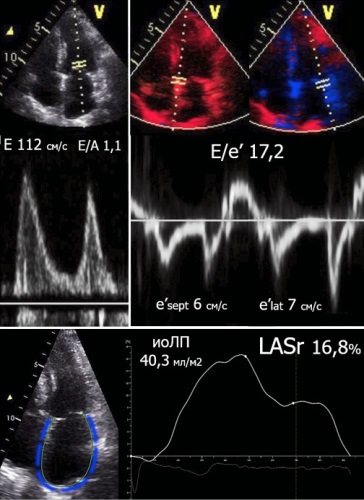

- Анализ резервуарной функции левого предсердия при эхокардиографии покоя в сочетании с дополнительными признаками угнетения диастолического резерва при диастолическом стресс-тесте составляют многофакторный/комплексный подход к диагностике сердечной недостаточности с сохраненной фракцией выброса.

Цель. Исследовать структурно-функциональное состояние сердца при подтвержденной сердечной недостаточности с сохраненной фракцией выброса (СНсФВ) в зависимости от тяжести диастолической дисфункции (ДД) левого желудочка (ЛЖ).

Материал и методы. Осуществлен анализ данных 303 пациентов с ДД ЛЖ (45,2% мужчин, средний возраст 66,3±6,0 года). Диастолический стресс-тест (ДСТ) проведен при недостаточном количестве критериев для заключения о СНсФВ по данным эхокардиографии покоя (n=251). В исследование включены 153 пациента с подтвержденной СНсФВ (35,3% мужчин, средний возраст 67,0±5,6 года). Группу I (n=101) составили пациенты со снижением диастолического резерва ЛЖ при ДСТ (E/e′ >14); группу II (n=52) — больные с выраженной ДД ЛЖ в покое, не требующие ДСТ для заключения о СНсФВ. Метод отслеживания движения пятен (speckle tracking echo) использован для оценки деформации резервуарной фазы левого предсердия (Left Atrial reservoir Strain, LASr).

Результаты. При анализе основных клинико-функциональных параметров между группами были выявлены статистически значимые различия по тесту 6-мин ходьбы (400,0 [360,0;440,0] м в группе I и 365,5 [310,5;401,5] м в группе II, соответственно; р<0,001) и концентрации N-концевого промозгового натрийуретического пептида (NT-proBNP) (257,7 [100,0;443,3] пг/мл и 412,0 [191,4;780,2] пг/мл; р=0,002). При проведении эхокардиографии покоя выявлены достоверные различия по индексу объема левого предсердия (иоЛП) (33,5 [29,2;40,1] мл/м2 и 40,8 [37,3;47,6] мл/м2; р<0,001), отношению E/e′ (11,3 [10,1;12,6] и 16,3 [14,9;19,2]; р<0,001), LASr (21,3 [19,5;24,7]% и 15,0 [12,5;17,3]%; р<0,001). По данным корреляционного анализа у больных СНсФВ выявлены связи умеренной силы: LASr и E/e′ (r=-0,538; р<0,001), LASr и иоЛП (r=-0,443; р<0,001), отмечено отсутствие связи между LASr и NT-proBNP (r=-0,157; р=0,060). При анализе ДСТ были выявлены статистически значимые различия по всем характеристикам увеличения ДН ЛЖ в группе I.

Заключение. Для пациентов с подтвержденной СНсФВ при увеличении давления наполнения ЛЖ характерно угнетение резервуарной функции ЛП и расширение полости ЛП. Фазовый анализ деформации ЛП и проведение ДСТ позволяет своевременно диагностировать СНсФВ.